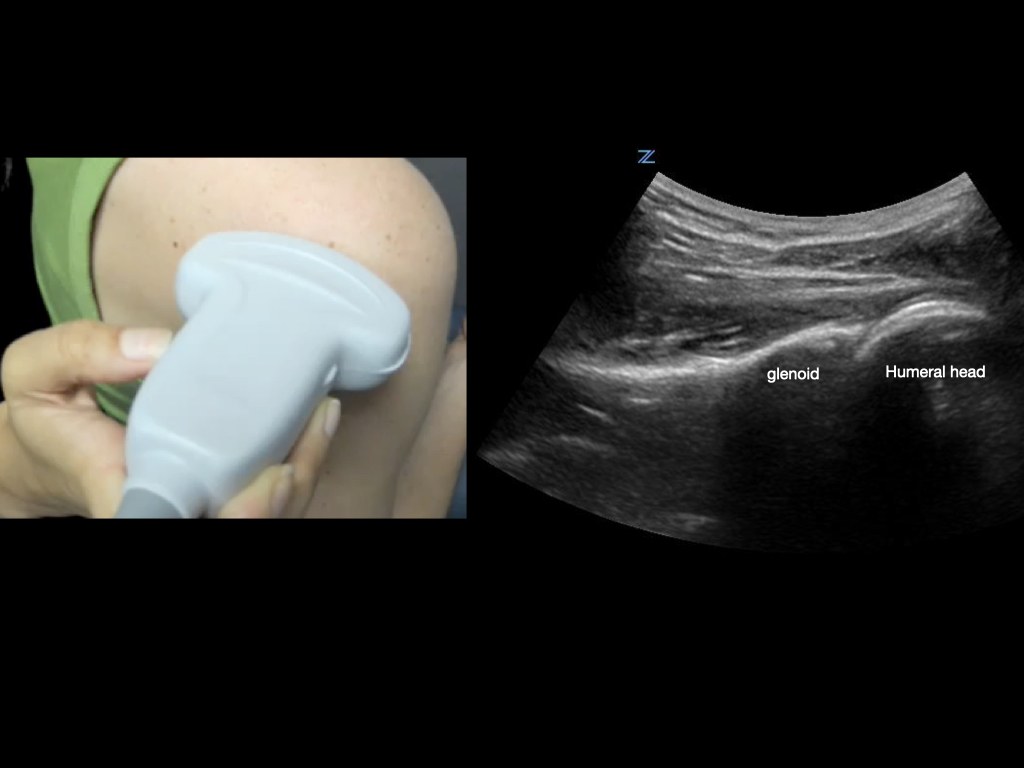

To best view the shoulder joint, consider using a curvilinear transducer. Align the transducer parallel and just inferior to the scapular spine, and slide the transducer out laterally until you are centered on the humeral head and glenoid.

Figure 4.

Transducer orientation when scanning the glenohumeral joint.

Take advantage of dynamic exams. For example, observe tendons moving through their range of motion; have the shoulder internally and externally rotate to observe the humeral head in the glenoid when evaluating for dislocation, etc.

Video 6.

Posterior shoulder internal and external rotation. This view (corresponding to Figure 4) shows the posterior humeral head rotating in the glenoid, confirming shoulder reduction, and demonstrating the rotator cuff tendon in motion.